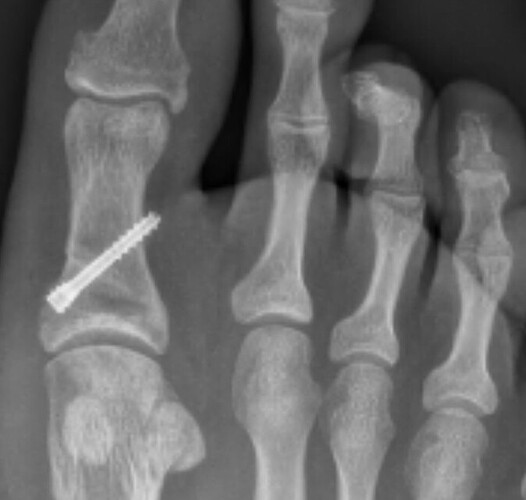

April 2024 I’d just come back from an amazing USA holiday and jumped back into a VFLW season. First game back hurt my big toe, don’t remember an action or a moment but this is where the pain started.

Fast forward to today, after 2 seasons of playing constantly in pain, rehab, countless exercises, taping, arts and crafts (IYKYK), cross training session, load management, MRI’s and X rays with no answer, training once a week just to get by, becoming besties with a moon boot, surgery in September and today 100 days since surgery a successful PAIN FREE return to run !! Yay

But its not just all of the physical pain and drain that goes with an injury, this injury had such a mental toll on me, more then I could ever had imagined. 2 years worth of uncertainty as to what the problem was and how we were going to fix it. Banter and running jokes about ‘Frogs dogs’ and ‘yeah I’m in a boot again’ ‘just wanted to get out of pre season’ are used to hide what was really being felt and bottled up inside. So many tears had at training, post games, in the car and in bed some visible to those around but most behind a closed door. I think it’s the uncertainty and constant worry that is definitely the worst feeling ever overtaking the physical pain.

I am fully aware it’s no ACL or career ending injury but I wanted to speak out to the other side of injuries that not everyone sees whether they are big or small. I am so thank full that I have the best circle of support people in friends, family, the EFC, sport psychs, physios and Doctors that have got me to this point today, a very happy girl who was once unsure if anything was going to fix her poor dog but today got through her first run pain free.